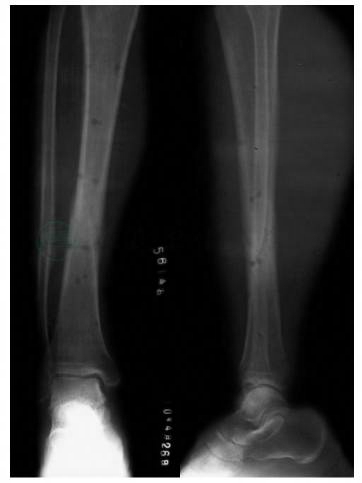

患者,男性,45岁。外伤后右小腿疼痛1天住院。入院时右小腿可及明显骨折征象。自带片显示,胫骨、腓骨中下1/3处螺旋骨折(图1)。

图1 胫骨中下1/3骨折术前